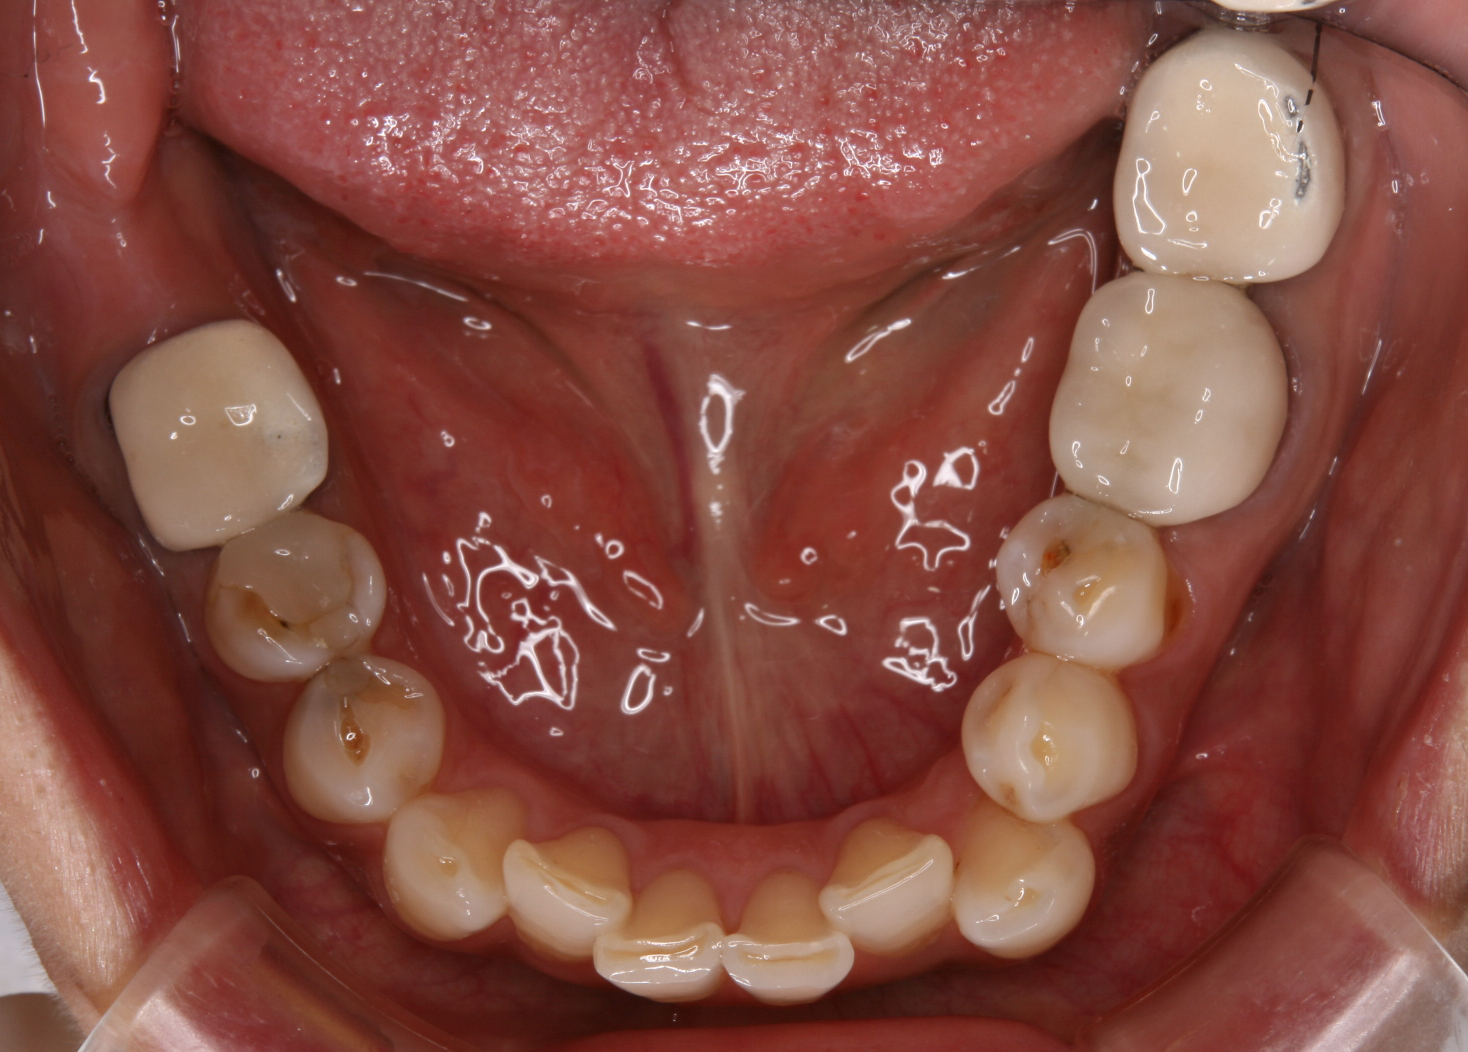

10年以上前に治療した奥歯のセラミックスクラウンをこの度きれいにしたいといらした患者さん。

写真で、右の奥歯2本、左の奥歯1本がセラミックスクラウンです。

セラミックスの下のメタルフレームが一部露出しています。

クラウンの前方の歯には虫歯が認められます。

歯と歯の間が黒くなっていたり、歯の中央に茶色いスポットがありますよね。